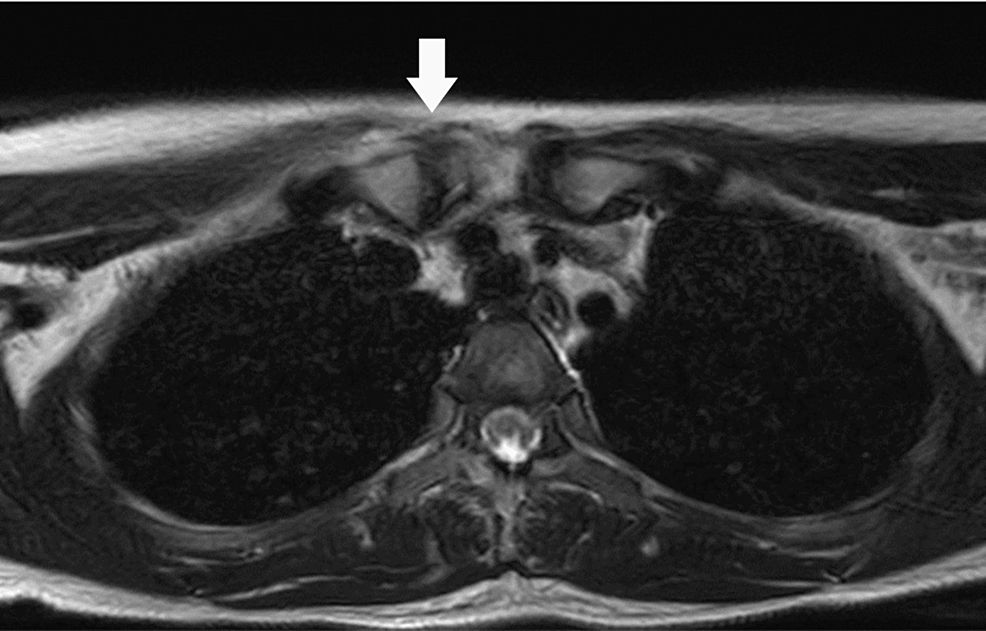

Sternoclavicular Septic Arthritis Due to Invasive Pneumococcal Infection After Type A Influenza Virus Infection

A 24-year-old female patient who had a type A influenza virus infection prior to admission visited our hospital complaining of a fever and right sternoclavicular pain. Blood culture was positive...

When a patient complains of gradually increasing chest pain after an influenza virus infection, SCJ septic arthritis should be considered in the differential diagnosis.